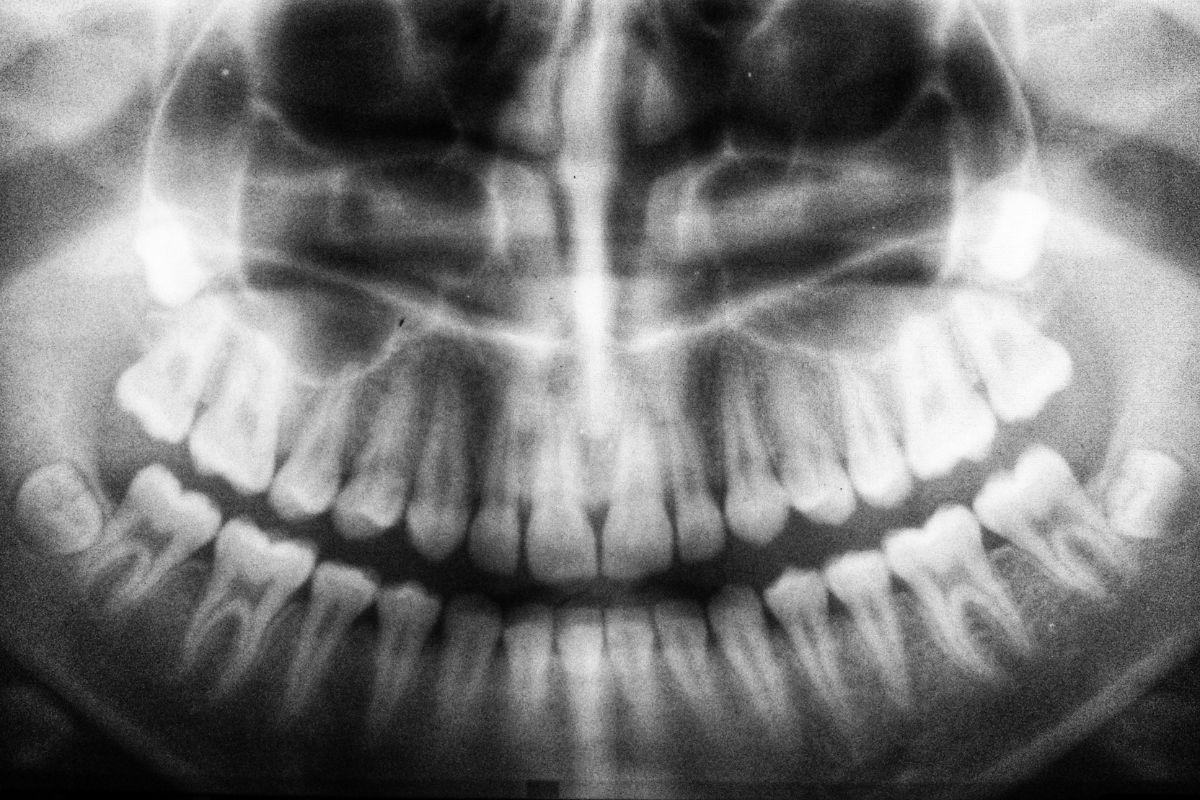

Il dentista può monitorare la loro crescita per valutare lo stato di salute e decidere se procedere o meno con la loro estrazione attraverso un esame radiografico. Questa valutazione è sempre meglio farla prima dei 18 anni d’età quando le radici non sono ancora completamente formate e il tessuto osseo è più tenero.